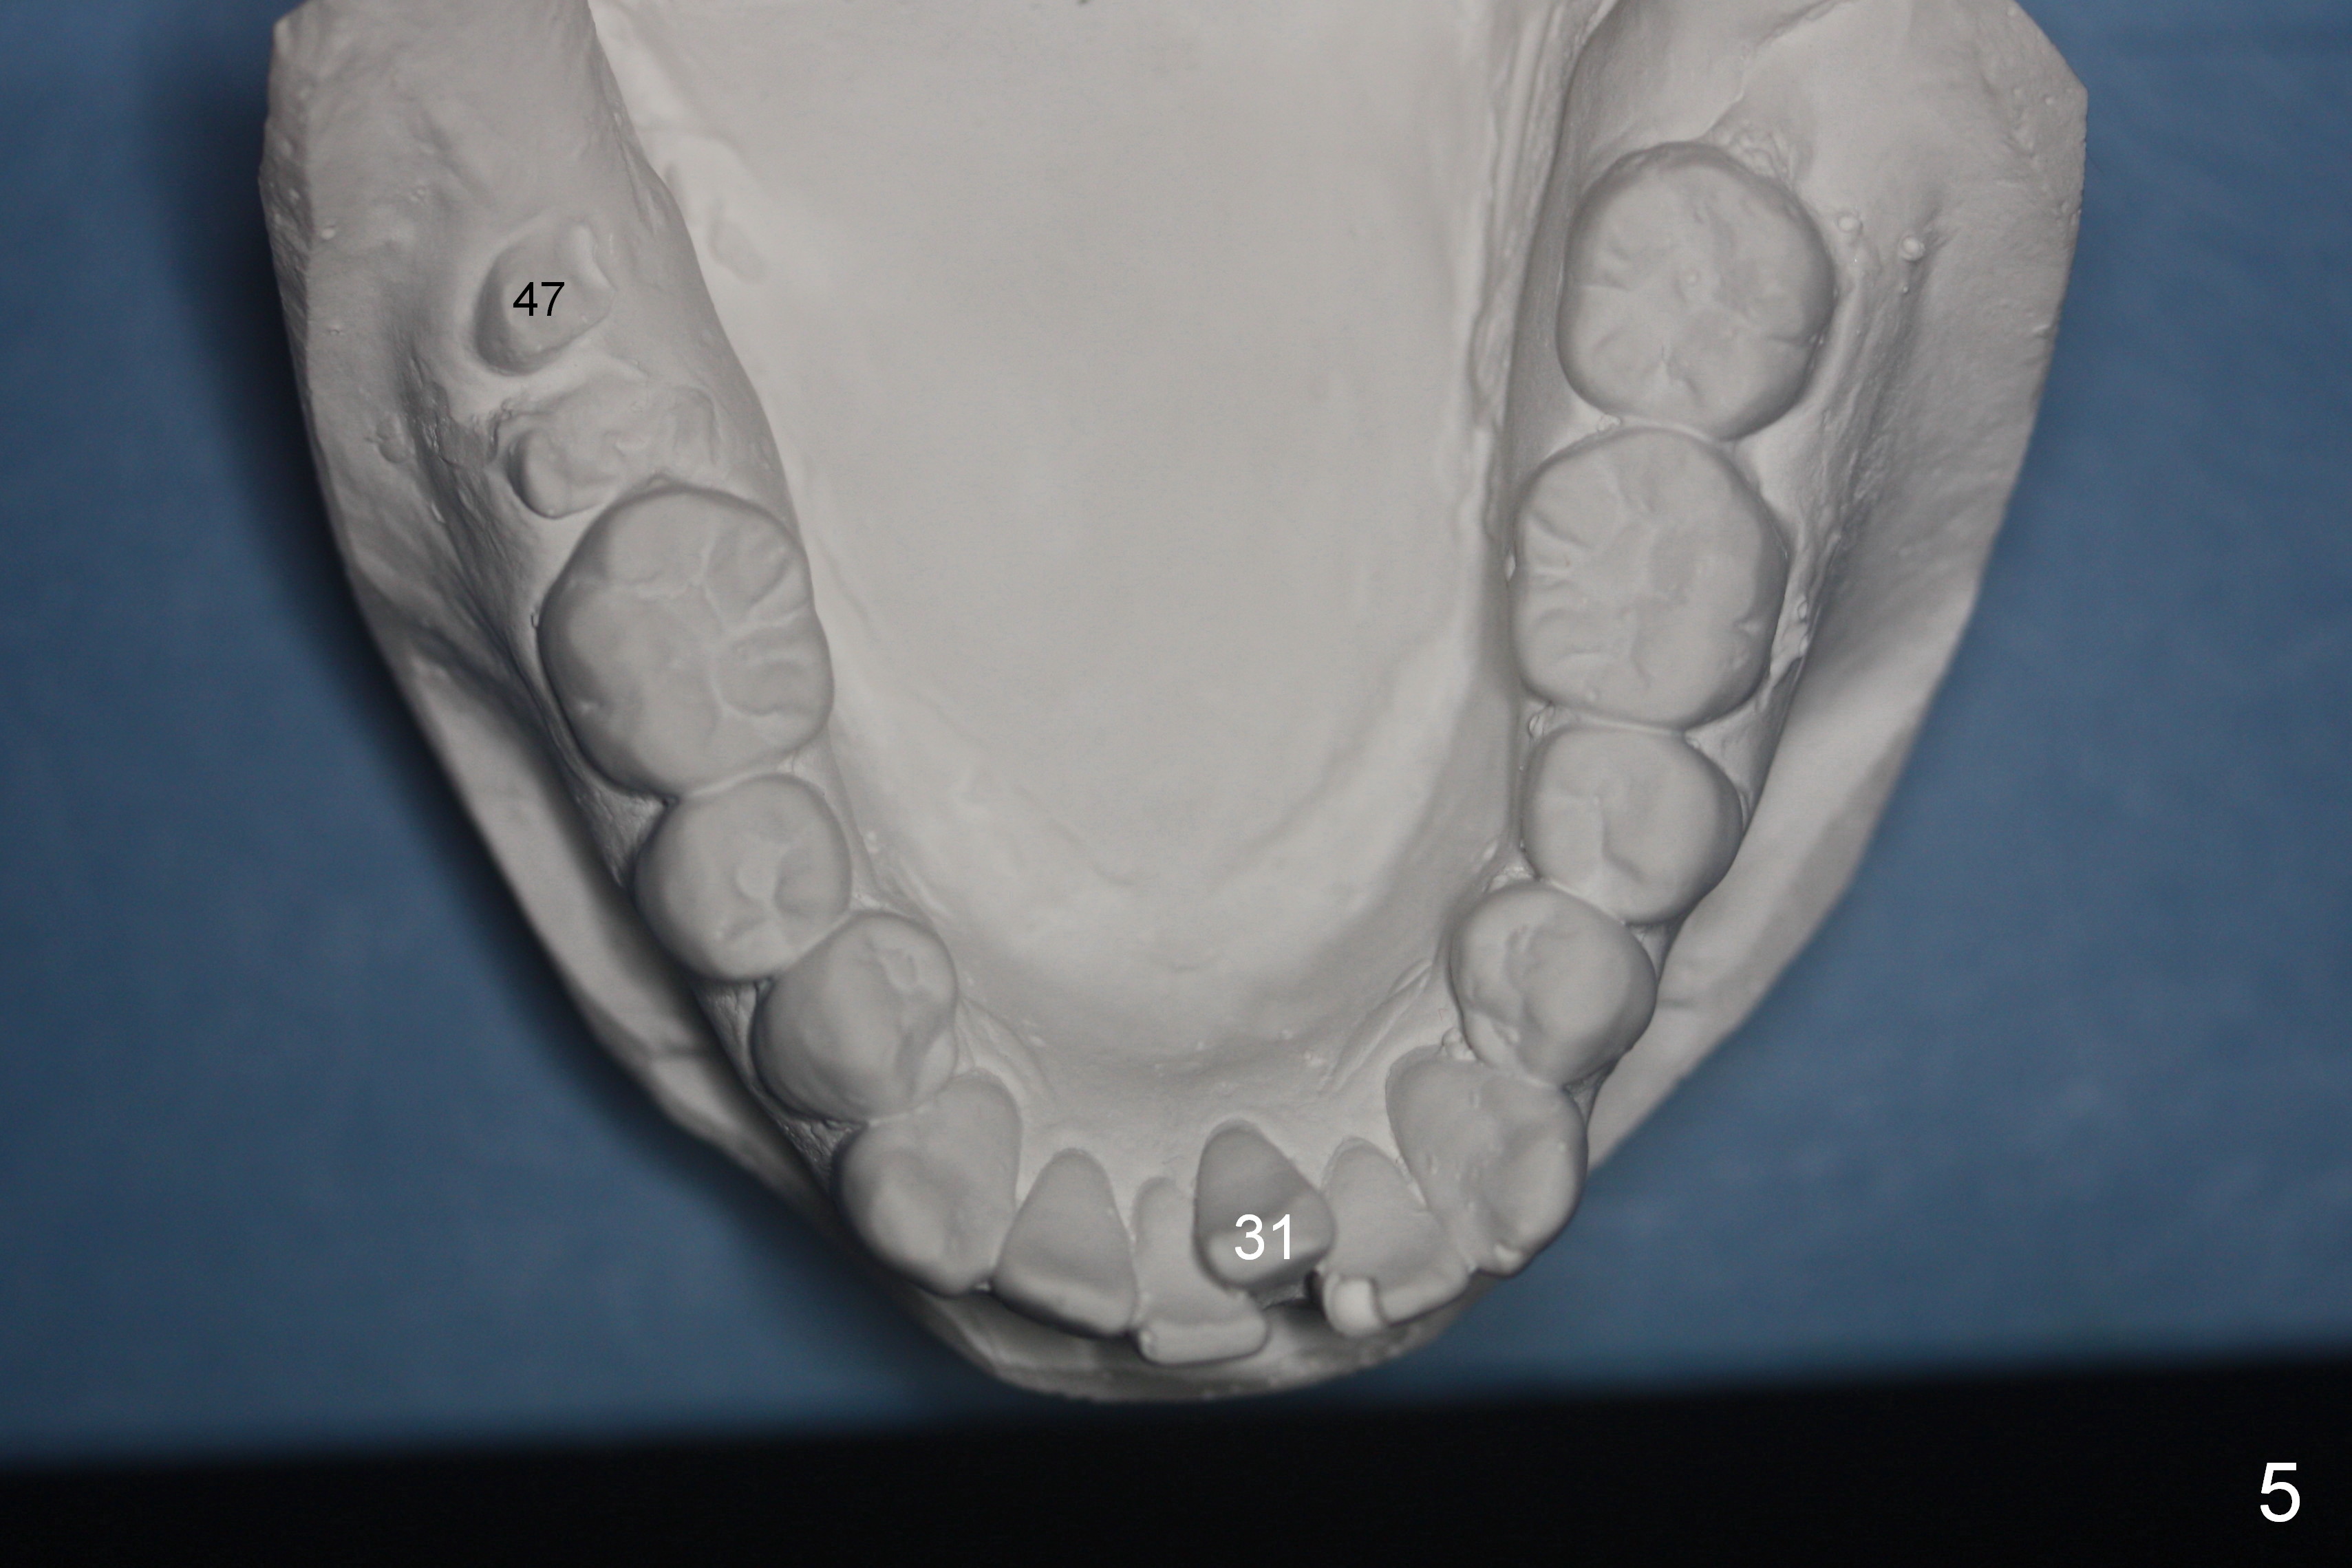

A 37-year-old man requests orthodontic treatment for severe crowding with 3 blocked-out incisors (Fig.1-5: 12,22,31 (International numbering, pronounced one two, two two and three one)). The upper and lower arches are pointed (Fig.4,5). The best option is extraction of 4 bicuspids (Fig.11-15).

His profile is convex with lip strain. After alignment of the anterior teeth, check the facial profile to determine whether it is necessary to distalize the anterior teeth or not. If it is, the distalization will be done with the aid of an implant at 47 (Fig.1,5 (residual roots)) and 3 mini-implants at the 3 other quadrants. An extra mini-implant will be placed at the upper right quadrant to intrude 17 (Fig.1 arrow).

There may be limited space for placement of these blocked out incisors. Do not have to place them at the time of bracketing until space has been created by arch wire sequence and open coil spring. It would be ideal to use labial torque brackets or place brackets upside down (Jenny's idea). In fact, the patient finishes ortho treatment in an orthodontist's office without intrusion of 17. Magicore will be placed at 47 to intrude 17 or simply for restoration.